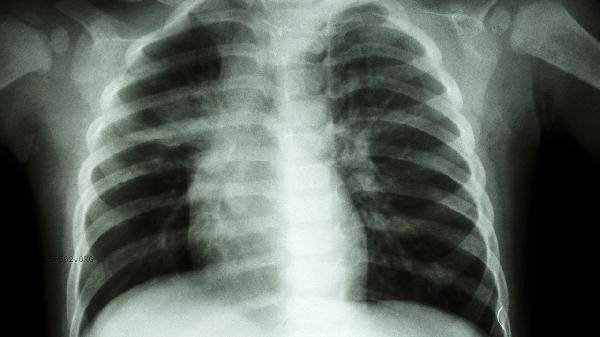

Chicken breast is a deformity where the sternum protrudes forward, often caused by abnormal calcium and phosphorus metabolism due to vitamin D deficiency in infancy, leading to bone softening and deformation. Calcium supplementation can provide the necessary raw materials for bone mineralization, but the effect of pure calcium supplementation is limited, and it must be combined with vitamin D to promote intestinal calcium absorption. Mild chicken breasts can be treated with daily supplementation of 400-800 units of vitamin D and appropriate calcium supplements, as well as exposure to sunlight to help the skin synthesize vitamin D. Most cases of deformities in children will gradually improve with growth. Moderate to severe chicken breast disease requires an increase in vitamin D dosage under the guidance of a doctor. If necessary, active vitamin D preparations such as calcitriol capsules should be used, and blood calcium and urinary calcium levels should be regularly monitored. During calcium supplementation, easily absorbable dosage forms such as calcium carbonate granules and oral calcium gluconate solution should be selected to avoid co administration with vegetables containing oxalic acid, which may affect absorption.